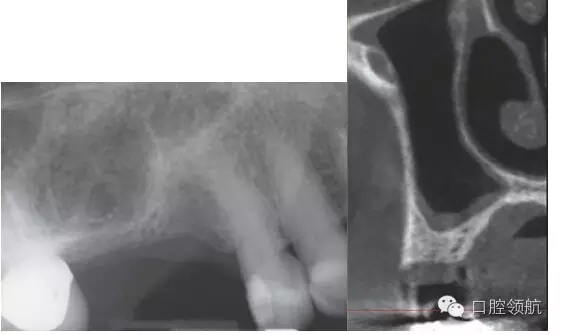

X線和CT顯示(圖1)種植前必須行上頜竇底提升術(shù)。CT顯示上頜竇頰側(cè)骨壁厚度大約為1mm,上頜竇黏膜輕度增厚,側(cè)壁黏膜薄。

圖1 術(shù)前X線片(左)和CT像(右)。